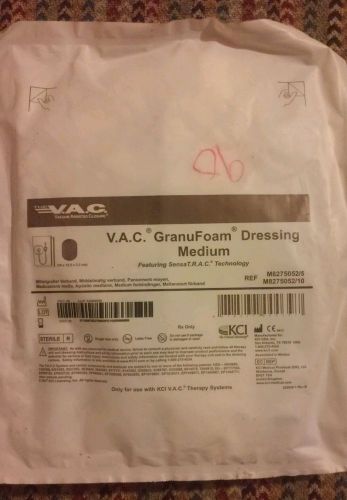

V.A.C. GRANUFOAM DRESSING MEDIUM Ref. M8275052/2 m8275052/10

KCI Vac Therapy GranuFoam Dressing Small. Lot Of 5. M8275051/5